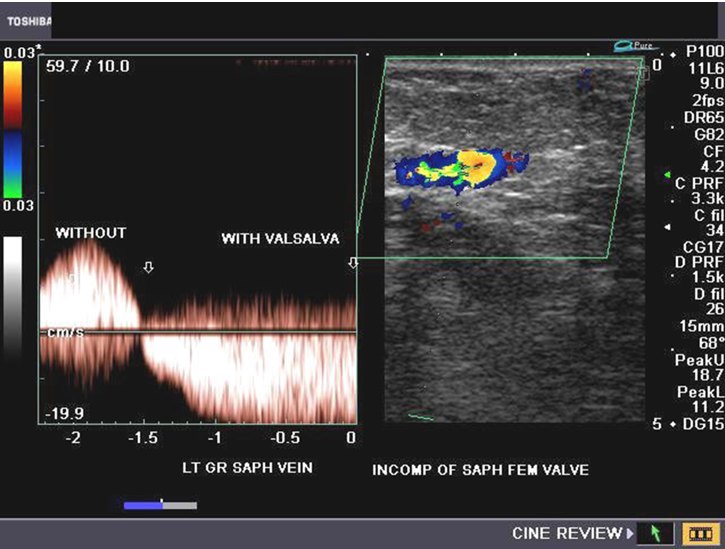

what is the normal response to valsalva maneuver

no flow while bearing down

return of flow upon exhaling

normal or abn?

norm

normal or abn

abn

normal

Qs what should you see on spectral doppler during valsalva maneuver when valves are not competent?

reversal of flow